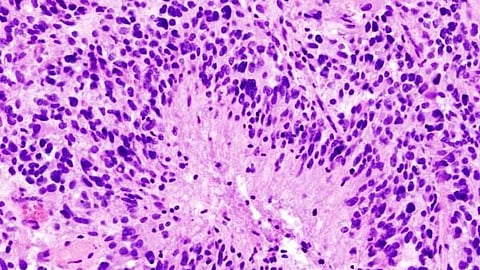

Glioblastoma is a lethal cancer that is always considered as an aggressive, stage 4 tumor at diagnosis with patients living an average of 15 months after diagnosis, Daddacha says. By the time symptoms like headaches and seizures emerge, the tumor already has progressed.

Standard treatment includes surgery to remove as much of the tumor as possible, radiation and chemotherapy.